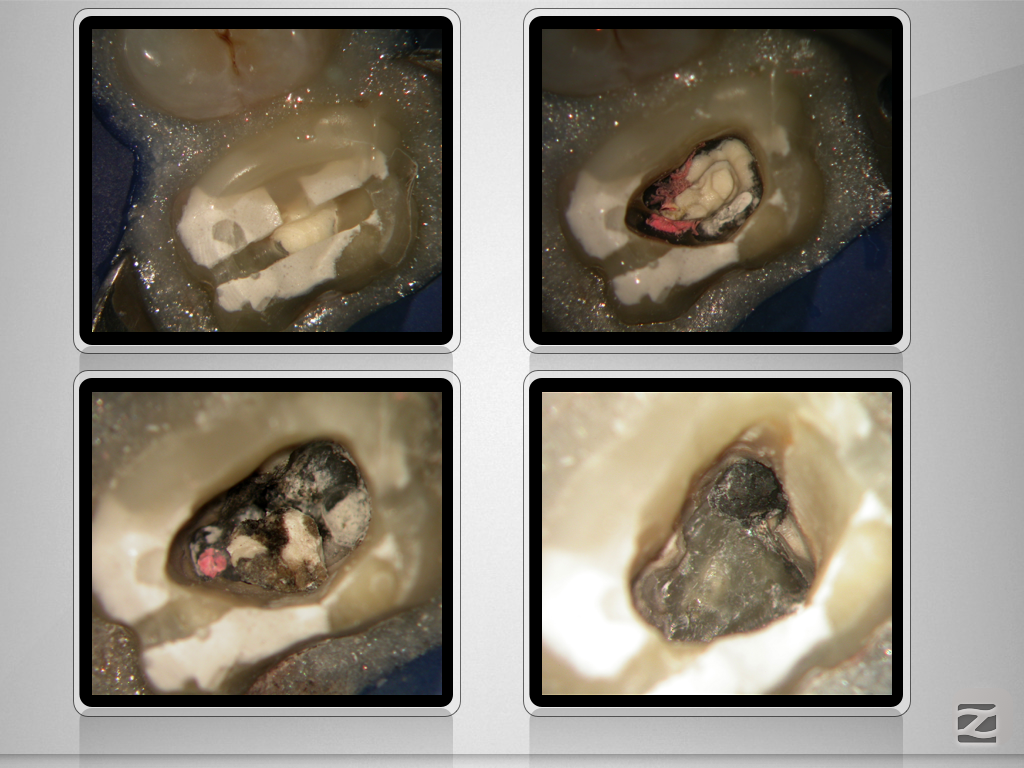

16d-006

Doppelt hält besser.